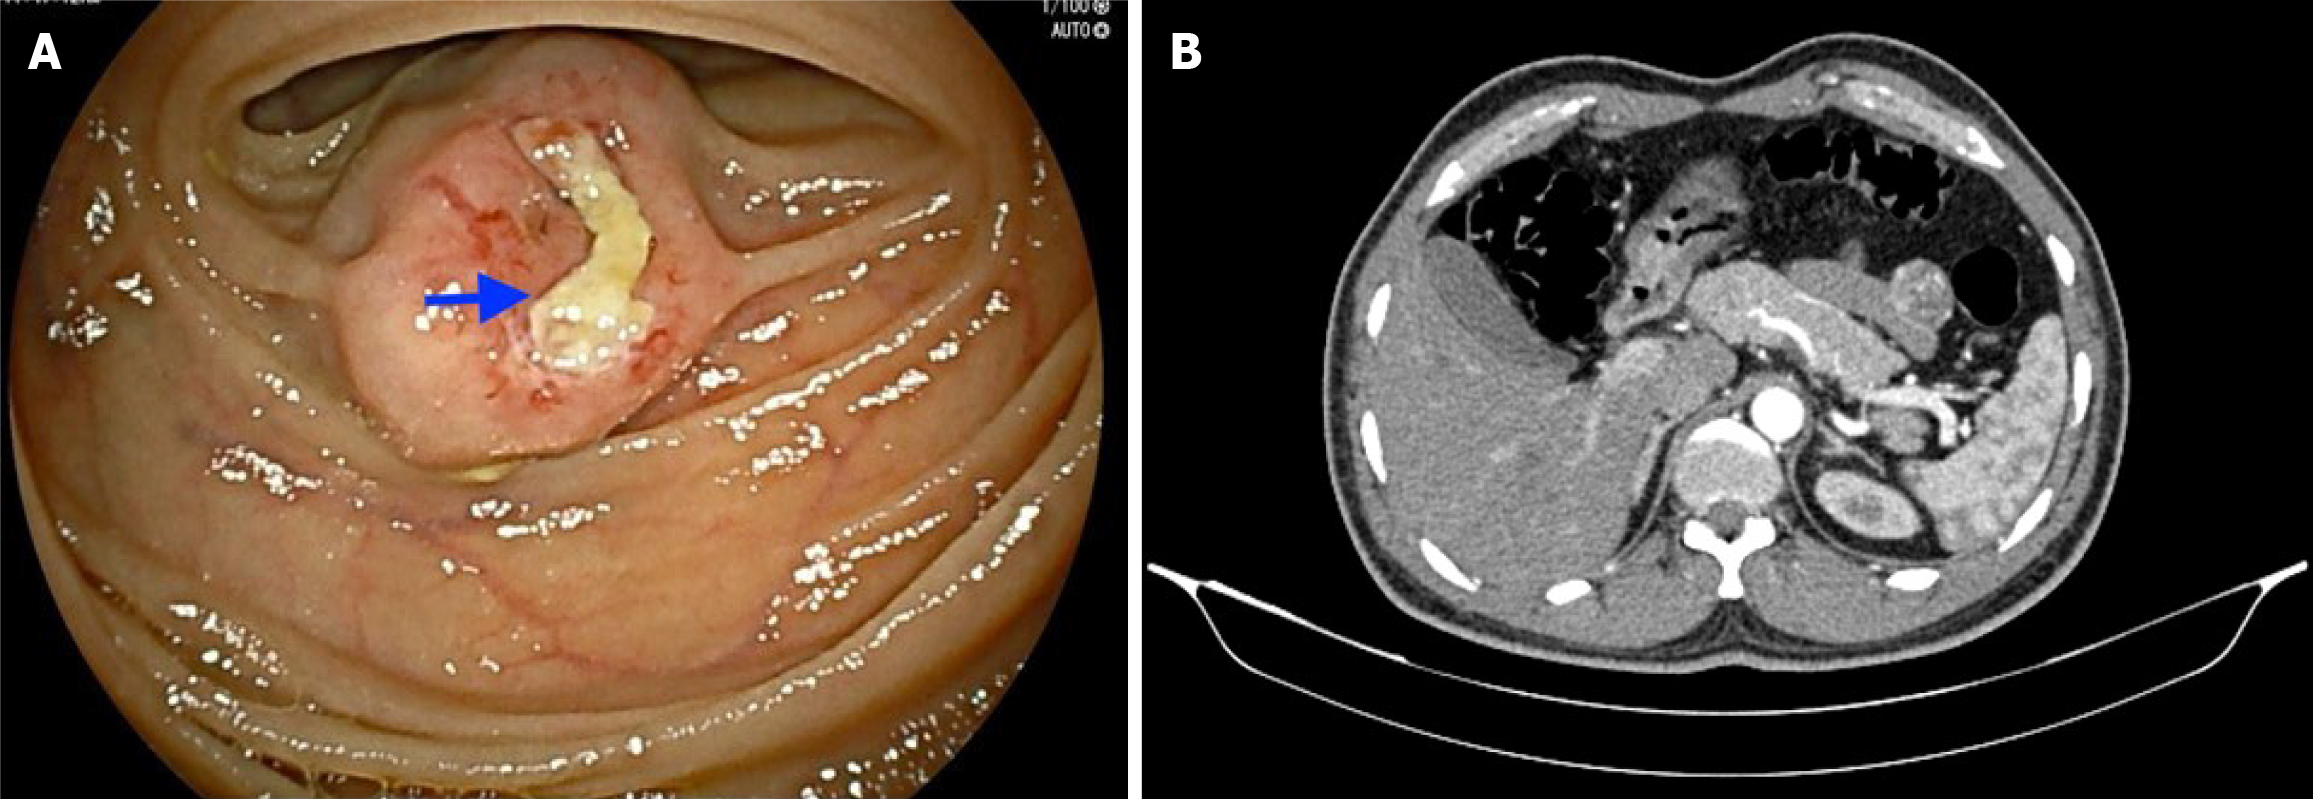

Figure 1 Imaging examinations.

A: Double-balloon enteroscopy image showing a subepithelial lesion (2 cm × 1.5 cm) approximately 150 cm distal to the duodenojejunal flexure and an overlying ulcer without any active bleeding; B: A contrast-enhanced computed tomography abdomen scan revealing a well-defined, round-shaped, homogenously enhancing solid exophytic lesion (30 mm × 22 mm × 26 mm) arising from the proximal jejunal loops without any obvious adjacent organ involvement, internal necrotic foci or calcification.